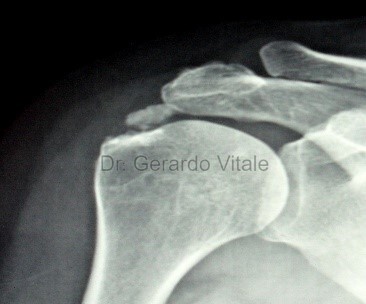

Diagnóstico:

El diagnóstico se basa en la presentación clínica, antecedentes del paciente, etc.

Estudios médicos que se pueden solicitar según el caso clínico son; Análisis de sangre (recuento de glóbulos blancos, marcadores inflamatorios etc.) Radiografías, Ecografía y la Resonancia Magnética pueden ayudar a distinguir las causas infecciosas de las no infecciosas.